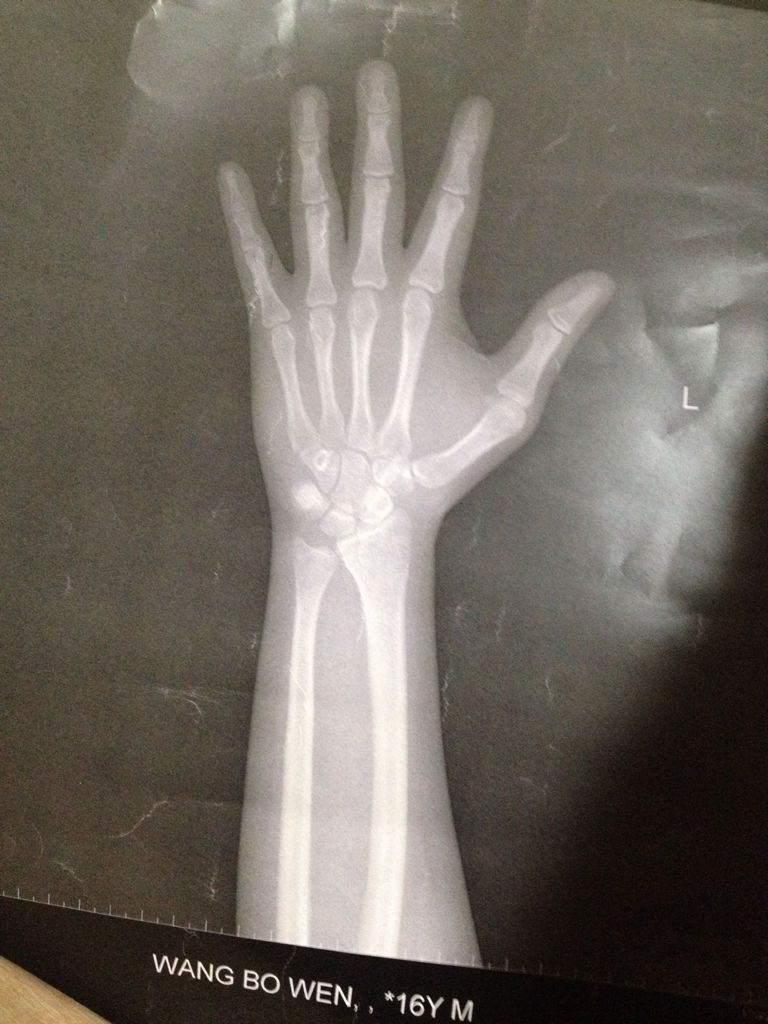

我今年十六岁半周岁,骨龄片(左手正位)是这样的,我还能长高吗,我才1.60米,男孩,希望帅哥帅姐们

我今年十六岁半周岁,骨龄片(左手正位)是这样的,我还能长高吗,我才1.60米,男孩,希望帅哥帅姐们帮帮我

图片不够清晰,完全录查葛看不到骨骺未愈合的痕迹,初步判断没有继续长高的机会。 还是转移注意力基孟,用过人的学识、品德、财富等弥补身高的不逼贸足吧